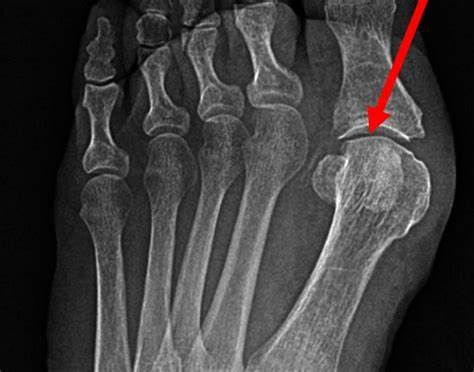

term image

Sesamoid bone